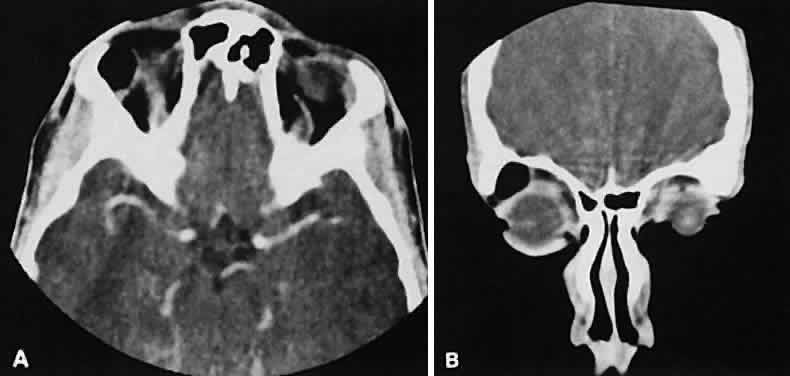

Optimal visualization of the orbit requires imaging from at least two planes. Axial slices should be oriented parallel to the optic nerve (-10 degreesto the orbitomeatal line) and no thicker than 3 mm. Axial views, because of volume averaging, may miss lesions located along the floor or roof. Additional views, typically coronal, can be obtained by reformatting data obtained during axial imaging or by direct coronal scanning.

Direct coronal views usually are preferable because of better resolution.6,7 They can be obtained by having patients lie either prone or supine, extending their neck, and angulating the gantry sufficiently to provide coronal imaging while avoiding artifacts from the teeth. Direct coronal scans also should be no thicker than 3 mm.

An appreciation for the various pathologic processes that affect the orbit is facilitated by an understanding of the normal orbital anatomy (Fig. 1). The orbit is a pyramid-shaped bony structure bounded inferiorly by the maxillary sinus, medially by the ethmoidal sinus, and superiorly by the frontal sinus. The sphenoidal sinus is situated posteriorly along the medial orbital wall and has a common wall with the optic canal. The lacrimal gland lies within its fossa located in the superior temporal aspect of the orbit and can be seen on both axial and coronal views.

The extraocular muscles (EOMs), with the exception of the inferior oblique, originate from the anulus of Zinn in the orbital apex. The inferior oblique takes its origin from the frontal process of the maxilla and is seen occasionally on CT imaging. The superior oblique, after originating from the anulus, courses along the superior nasal orbital wall just above the medial rectus muscle before passing through the trochlea. The rectus muscles conveniently form a muscle cone, which is sometimes helpful in terms of differential diagnosis. Before thinner axial slices and multiplanar imaging were available, an enlarged inferior rectus muscle often was imaged as an apical mass, especially if dysthy-roid optic neuropathy was present. The importance of imaging from two different planes cannot be overemphasized in this situation.